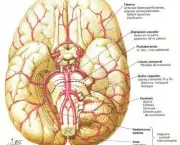

O Aneurisma Cerebral pode ser definido basicamente como uma dilatação anormal de uma das artérias do cérebro. Essa dilatação pode levar a ruptura dessa artéria, o que gera sangramentos que seguem para um espaço do cérebro chamado de “espaço subaracnóide”.

Em geral uma ruptura inicial de Aneurisma Cerebral leva cerca de 1/3 dos pacientes a morte, os que sobrevivem tem o risco de morte somado a cada novo episódio. O mais interessante a respeito do Aneurisma Cerebral e que poucos sabem é que muitas pessoas nascem com o aneurisma, o que os médicos chamam de Aneurisma Congênito.

Esse aneurisma pode aumentar e se romper, essas formações podem se romper em qualquer momento da vida, mas é mais comum na quarta ou quinta década da vida. As mulheres possuem mais chances de desenvolver aneurismas do que os homens e em mais de 20% dos pacientes é possível observar a existência de mais de um Aneurisma Cerebral.